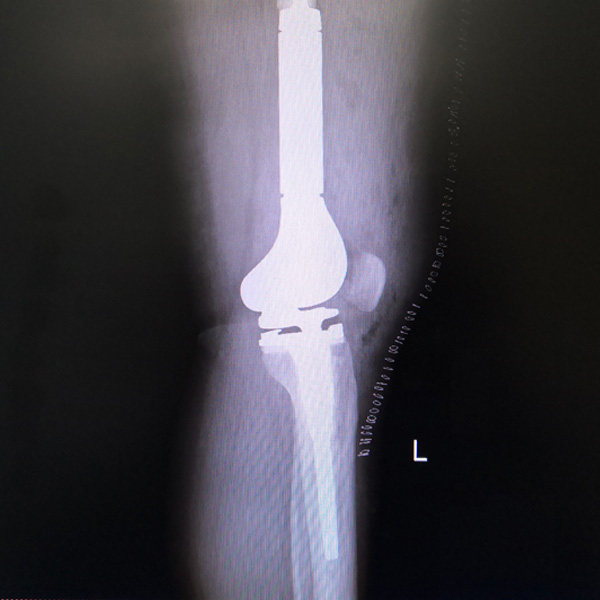

骨肉瘤手術

患者張某,女,14歲,診斷為“左股骨遠端骨肉瘤”,當地醫院因為醫療技術和能力的限制,只能考慮截肢手術?;颊呒覍偻ㄟ^平臺推薦,指定到哈......